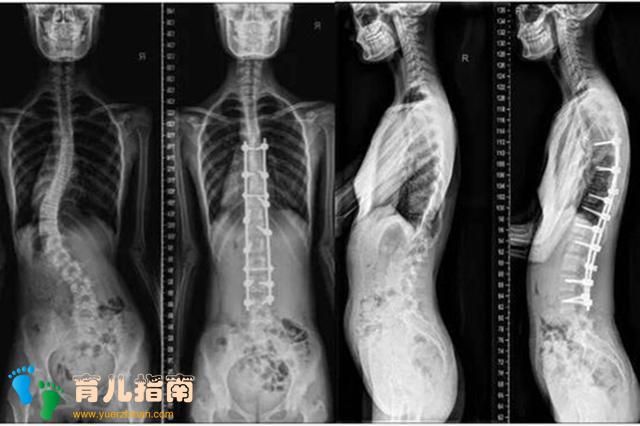

脊柱侧弯是一种通俗说法,医学上称为脊柱侧凸”,是指脊柱的冠状位、矢状位和轴位等序列异常,属于一种三维畸形情况。

医学上通过全脊柱X线片观测的诊断标准,是cobb角大于10度。

但一旦程度很重,就会影响到生长发育,出现身体变形情况,甚至累及心肺功能、脊髓,最终导致瘫痪。

这是青少年和儿童多发的一种畸形疾病,轻者日常多加观察即可,重者必须通过手术治疗,家长万万不可马虎大意。

胚胎时期的脊柱分节不完全、一侧有骨桥或一侧椎体发育不完全等单种或混合因素,都可能造成先天性的脊柱侧弯,X线片上能明显发现脊柱发育畸形的情况。

如果角度在20-40度之间,可以选择配戴矫正支具,但这比较麻烦,需要根据孩子的具体弯曲程度和部位量身定做,且要定时照片子来监测矫正作用。

包括睡觉时间在内,每天要佩戴20小时以上,隔半年还要拍片复查,更换支具,比较繁琐。